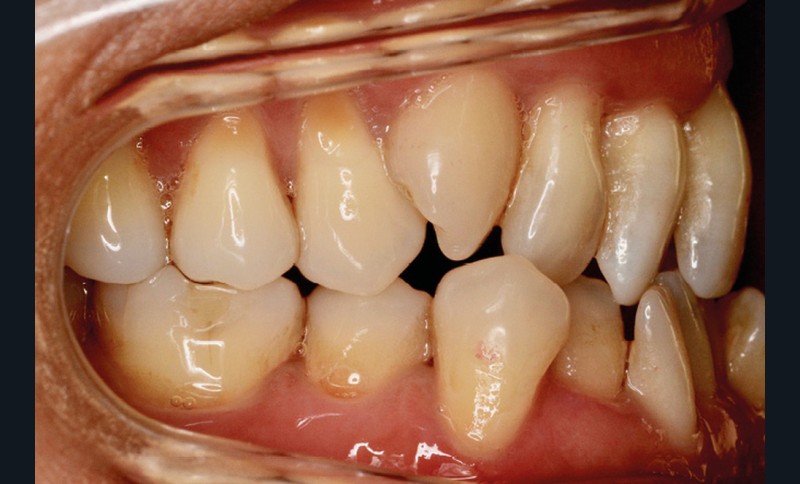

Présentation du cas (fig. 1 à 9)

Sur le plan squelettique, on retrouve une classe III de Ballard par hypomaxillie, dans un schéma facial hyperdivergent.

Sur le plan dentaire, la patiente est en classe III droite et gauche, canine et molaire de 6 mm, avec une occlusion inversée antérieure localisée à 11, 12 et 22. Elle présente une dysharmonie dents-arcades sévère, une agénésie d’une incisive mandibulaire est à signaler, et les troisièmes molaires ont été extraites à l’âge de 21 ans.

Au niveau fonctionnel, on note un bruxisme statique avec contact permanent entre les dents maxillaires et mandibulaires. La patiente présente des prématurités en relation centrée sur les incisives, le guidage en propulsion est perturbé et des interférences multiples sont retrouvées en latéralités droite et gauche.